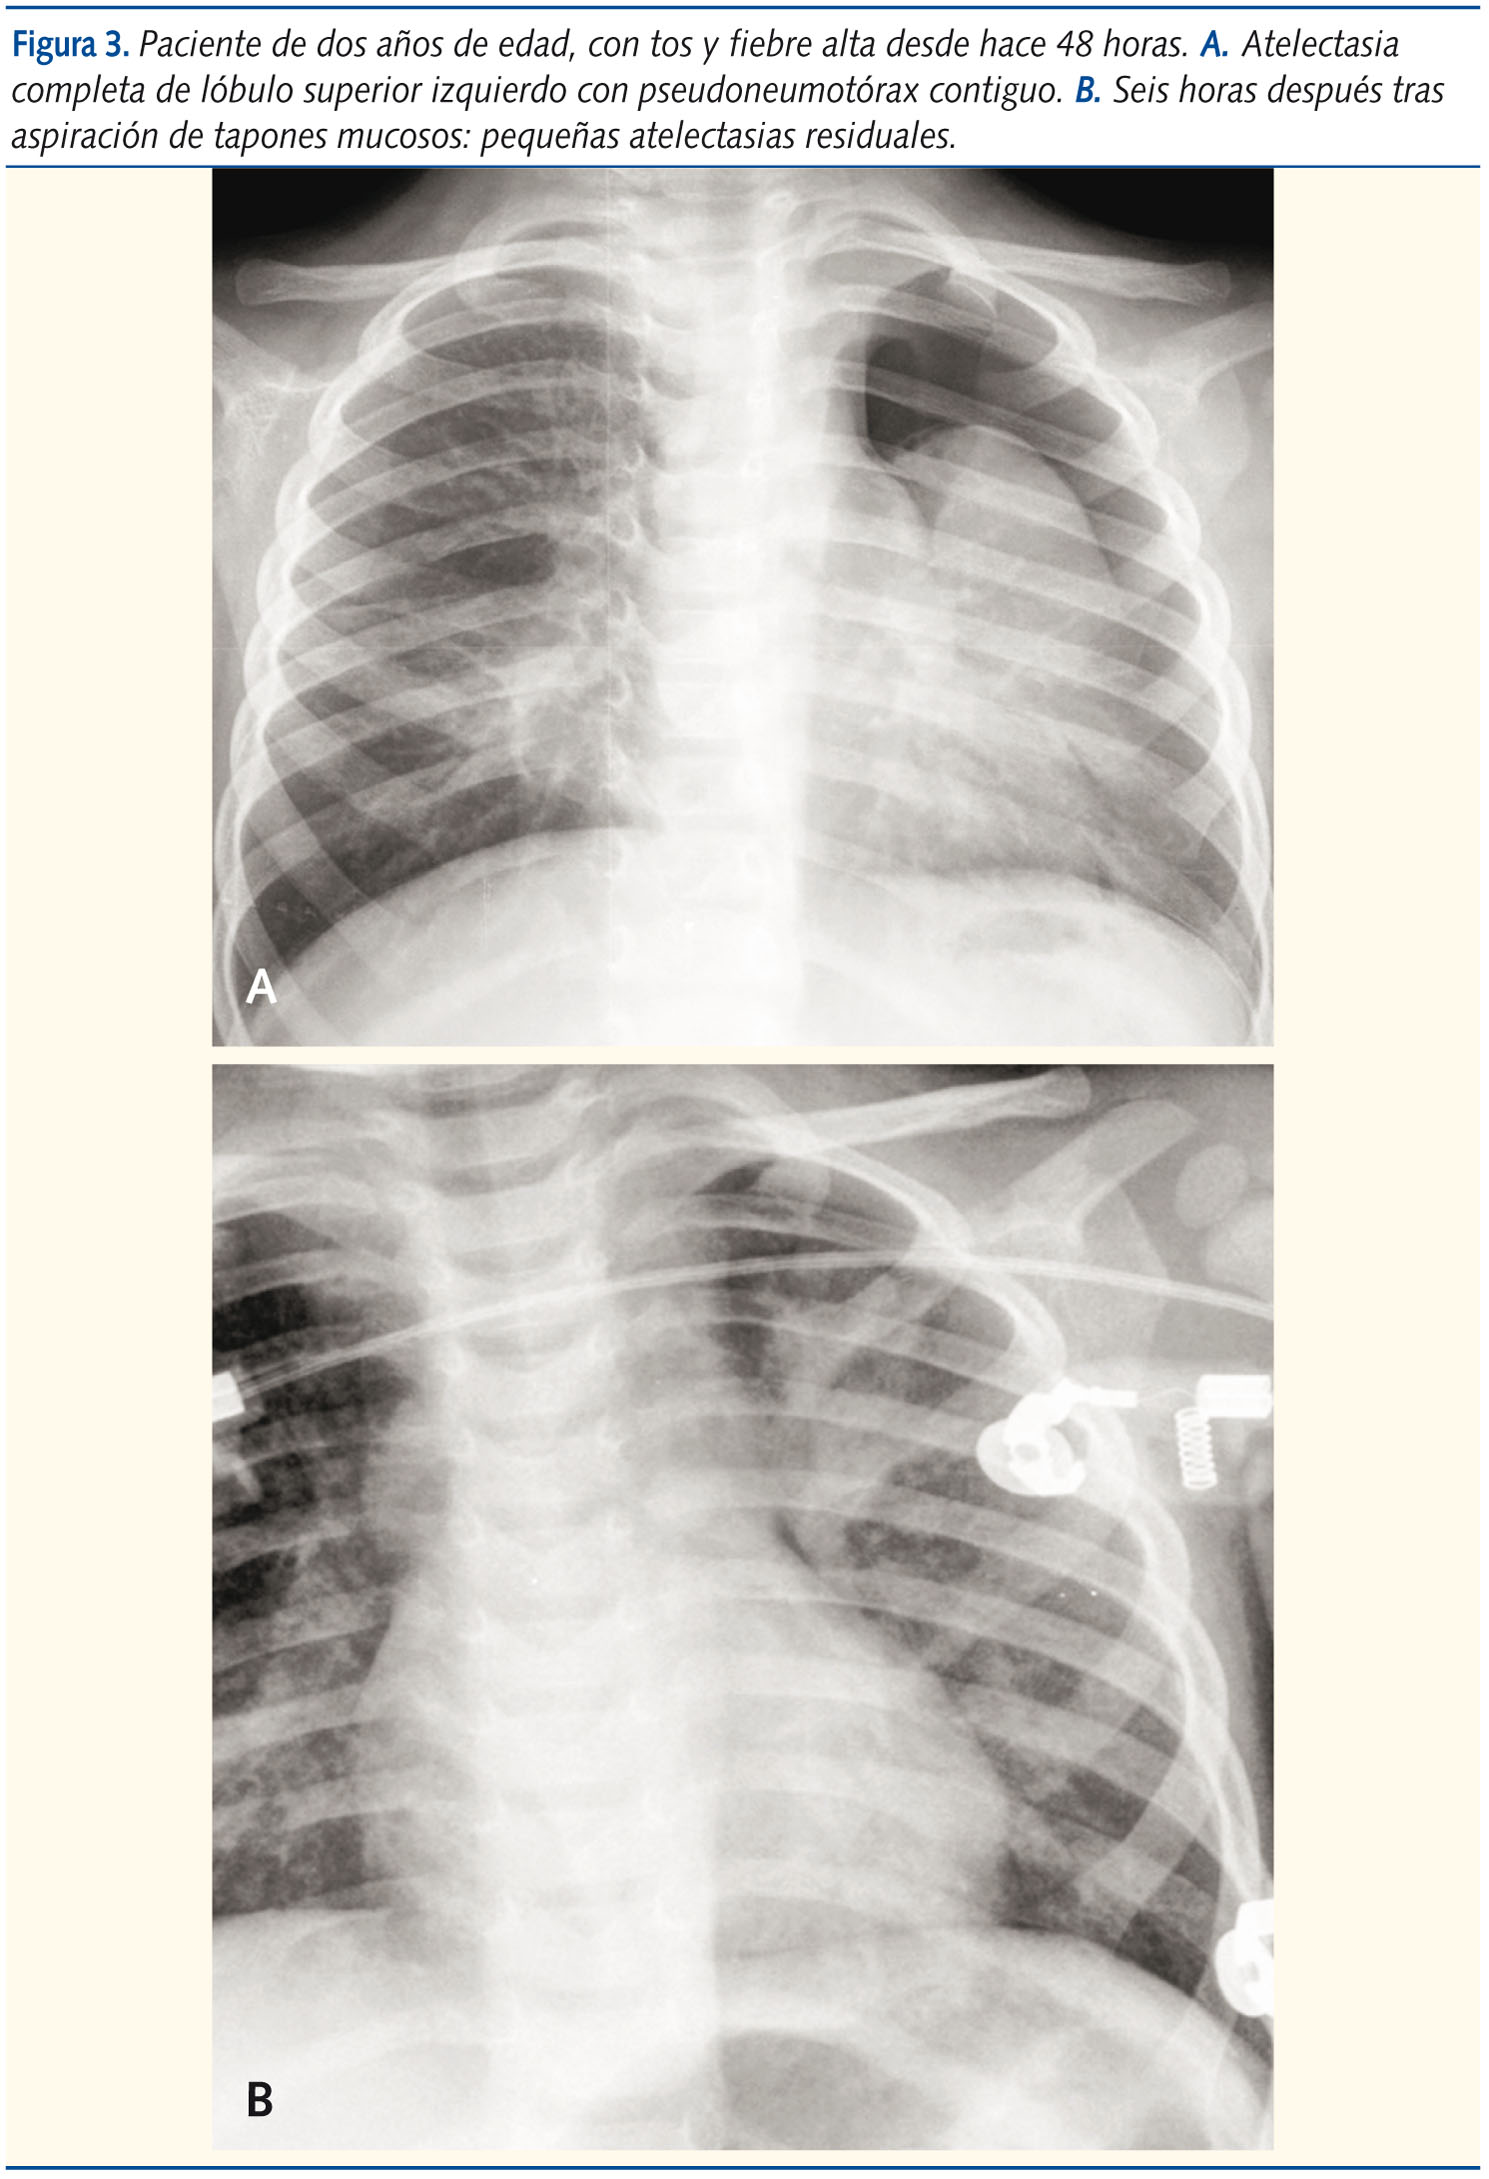

Contiguo a la atelectasia aguda de un lóbulo pulmonar, especialmente de los superiores, sobre todo derecho, por oclusión del bronquio correspondiente por cuerpo extraño o tapón mucoso en contexto de bronquiolitis, asma o proceso infeccioso (figura 3). Descrito por Berdon19, se sugiere que este gas no es aire, sino mezcla de componentes, predominantemente nitrógeno, procedentes de estructuras vasculares vecinas.

La atelectasia de larga duración obliga a contemplar la posibilidad de tumor intrabronquial a identificar mediante TC. El más frecuente es el tumor carcinoide (90%)20.